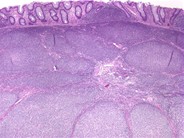

Follicular lymphoma (grade 1/3) in a hepatic flexure polyp - 4.

Author: Julia M. Braza

Category: Lymphoma: Mature B-cell and Plasma cell Neoplasms > Low-grade B-cell lymphoma > Follicular Lymphoma

Published Date: 11/01/2007

The infiltrate is predominantly comosed of small lymphoid cells with irregular nuclei and small amounts of cytoplasm. There are occasional larger lymphoid cells with vesicular chromatin and distinct nucleoli (<5/HPF).